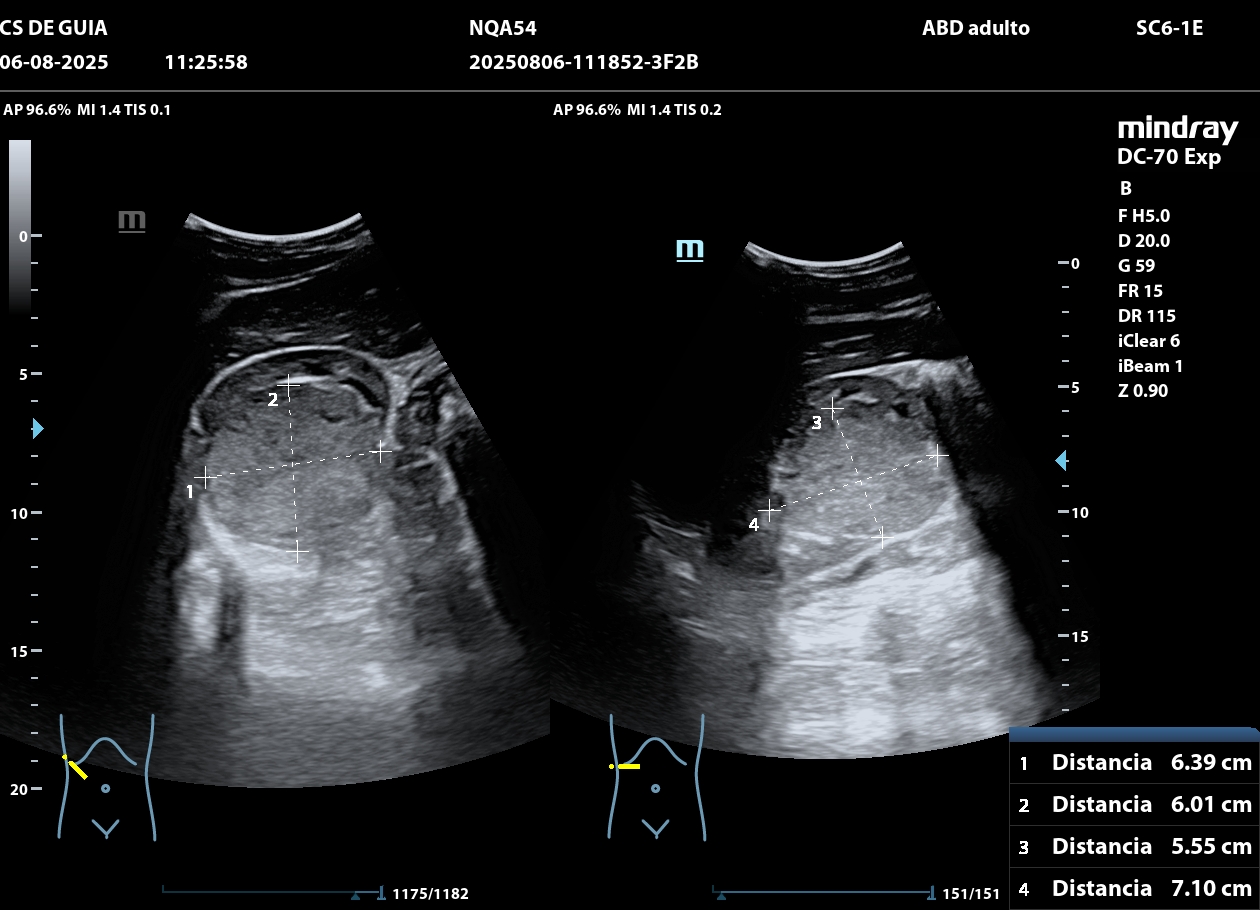

Hallazgos ecográficos

Ecografía: riñón derecho una masa isoecogénica de 7,1 x 6,3 cm de diámetro en médula renal que no deforma la cortical, vascularización periférica y sin sombra posterior.